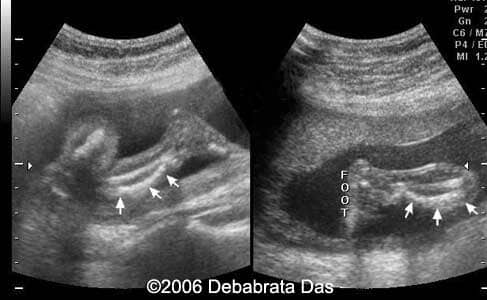

Case report: This is a 22-year-old primigravida referred for a routine anomaly scan at 22 weeks. She has a family history of consanguinity. Our scan revealed significant lower limb shortening. The femur and tibia showed bilateral bowing. Fibulae appeared normal. The mineralization of the bones was adequate. The upper limbs seemed normal. The axial skeleton showed 11 pair of ribs. No abnormal fetal chest narrowing. Fetal facial features were unremarkable. A camptomelic dysplasia was suspected. The pregnancy was interrupted. The radiograms showed bilateral bowing and shortening of tibia and femur.